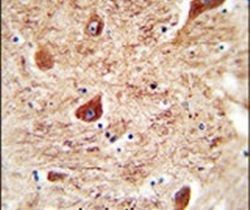

- Main image

- Experimental details

- Immunohistochemistry analysis in formalin-fixed, paraffin-embedded human brain tissue using a CORO7 polyclonal antibody (Product # PA5-24255), followed by HRP-conjugated secondary antibody and DAB staining.